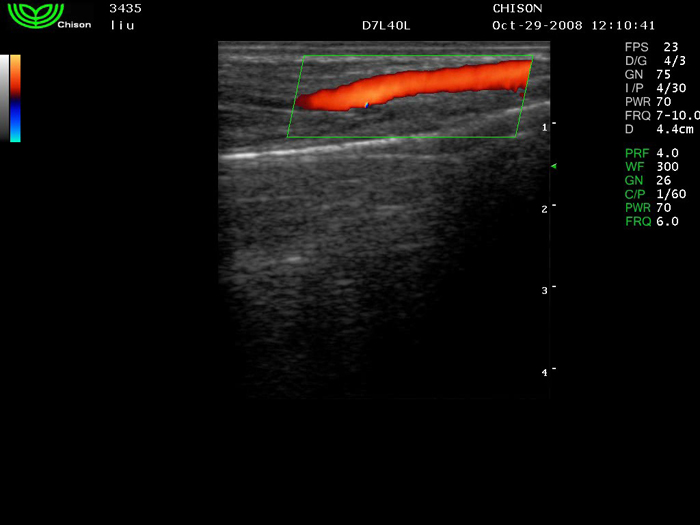

D7L40L 7.5МГц, линейный.

4.0МГц – 13.0 МГц. Применения: грудь, малые органы, нервы, сосуды, венозная катетеризация, мышцы и скелет, управление биопсией. |